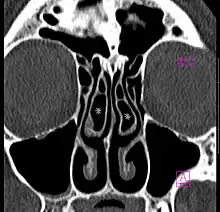

Bilateral concha bullosa, larger on the left